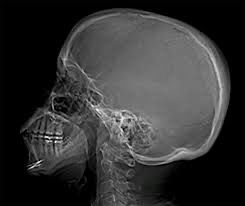

Xray에서 몸과 시선이 왼쪽을 향하고 있다면 이미지상 정면에 보이는 것은 오른쪽 측면이에요 즉 측두골을 본다면 오른쪽 측두골이 보이게 됩니다 xray는 촬영 방향에 따라 좌우가 반대로 보일 수 있어 정확한 판독을 위해 의료진의 설명을 듣는 것이 좋아요!

보통은 첨부하신 사진과 같이 촬영이 된 두개골 x-ray의 경우에는 우리가 측두골을 본다고 하였을 때 왼쪽편 측두골을 보고 있는 것이라고 생각하시면 되겠습니다. 다만 이는 어떻게 촬영을 하였는지, 어떻게 영향을 저장하였는지 등 요인들이 영향을 끼칠 수 있기 때문에 보통 화면의 좌측이나 우측 위에 우측이라면 R, 좌측이라면 L 하는 식으로 라벨링을 합니다.

몸과 시선이 왼쪽을 향하고 있다면 좌우 반전을 하지 않았다면 우리가 보는 측두골은 왼쪽 측두골일 가능성이 높으며 사람이 바라보는 방향의 축두골을 보는 것이라고 이해하시는것이 좋습니다.

X-ray 촬영에서 왼쪽을 향하고 있는 경우, 촬영된 이미지는 왼쪽 측두골을 보고 있는 것입니다. 즉, 몸이 왼쪽을 향하고 있으면 X-ray 상에서 오른쪽 측두골이 정면에 보이는 형태로 나타나게 됩니다. 이때, X-ray에서 나타나는 이미지는 환자의 몸을 기준으로 반대로 반영되기 때문에, 왼쪽을 향하고 있을 때 오른쪽 측두골이 보이는 것입니다.

엑스레이사진만으로는 오른쪽인지 왼쪽인지 확인할수없습니다 따라서 엑스레이사진에 R이나 L로 위치를 표시해주기때문에 엑스레이 사진을 전체적으로본다면 확인할수있습니다 감사합니다~